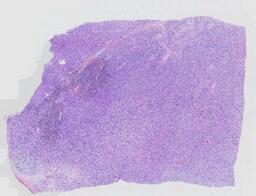

临床资料: 患者,女性,59岁,部位:左侧臀部浅表肿物。临床:左侧臀部结节半年,伴轻度压痛;术中见:左侧臀部褐色结节,边界清楚,质韧。既往史:宫颈恶性肿瘤,具体不详。

大体所见: 带梭形皮瓣的组织一块,大小1.4cm×0.7cm×0.6cm。切面灰白、实性、质中。